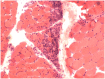

Figure 5-2.

Dermatomyositis. Muscle biopsy demonstrates classic perifascicular atrophy of muscle fibers (hematoxylin and eosin stain).